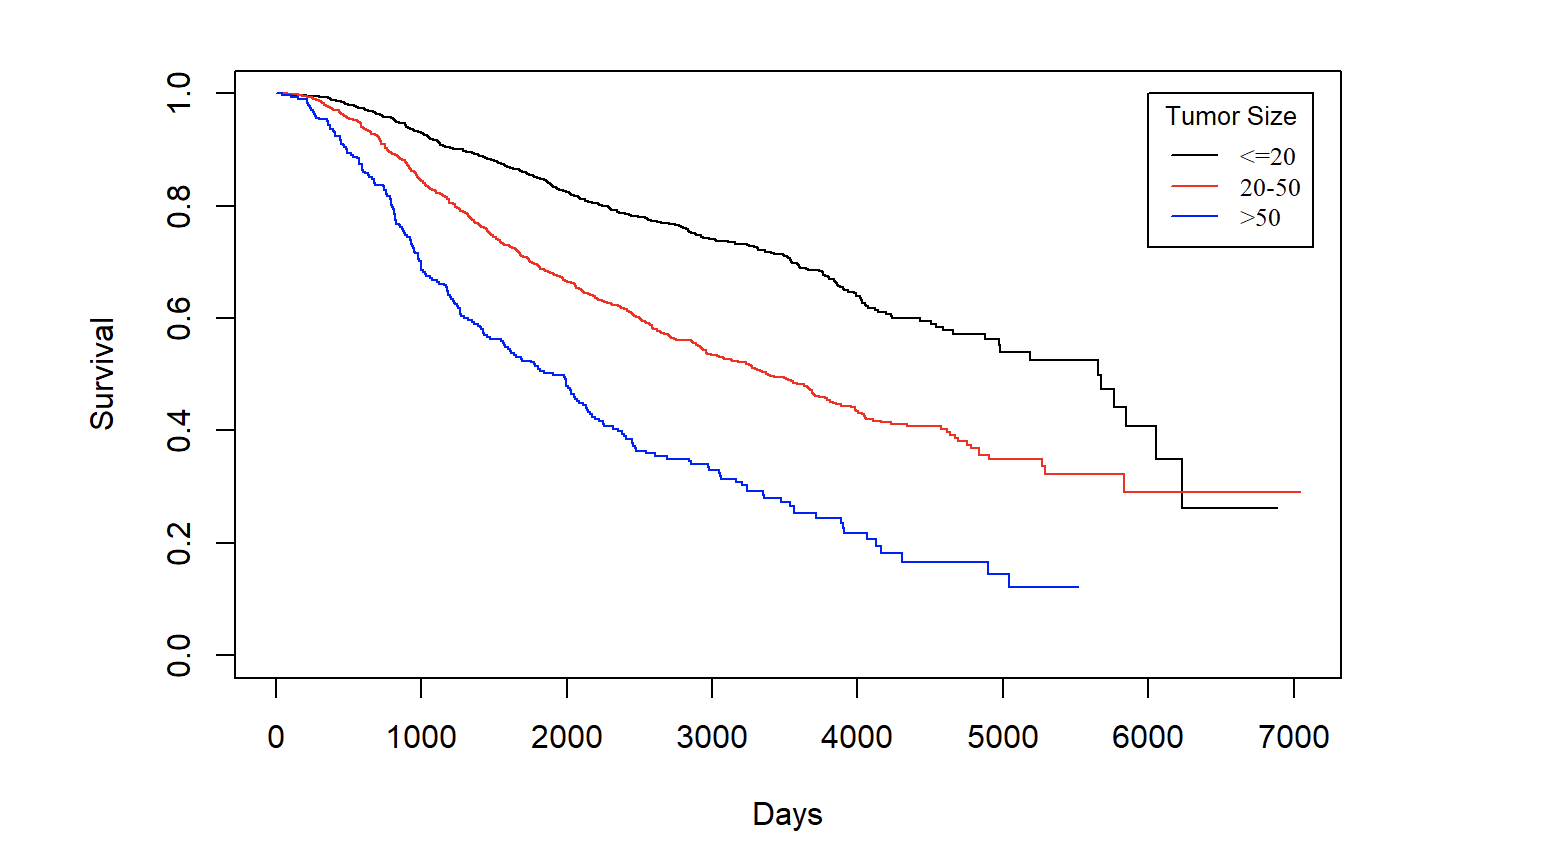

Analysis of Breast Cancer Treatments

How do differing breast cancer treatments compare in effectiveness? When considering which treatment is best, we would expect for more invasive procedures to lead to greater survival outcomes, but is this truly the case? Using data from the Netherland Cancer Institute, we were able to analyze survival outcomes across different treatments. In this analysis we compare outcomes for patients who underwent chemotherapy, hormonal, and amputation treatments and determine if any of the treatments leads to longer survival time compared to others.

What are the key factors affecting the survival of breast cancer patients?

Cancer has become a critical health problem. Among all sorts of cancer, breast cancer is the second common one in American women. Motivated by providing statistical insight into this disease, my teammate and I analyzed breast cancer data from Rotterdam Tumor Bank. This analysis aimed to investigate potential key factors affecting the survival time of breast cancer patients and also promote the awareness of breast cancer screening.

Factors that Affect Breast Cancer Survival — A Survival Analysis with Rotterdam Dataset

According to World Health Organization, Cancer is a leading cause of death worldwide, accounting for an estimated 9.6 million deaths in 2018. And amongst all cancer types, breast cancer(along with lung cancer) has the top cases of death: 2.09 million cases in 2018. According to the CDC, Breast cancer is also the second most common cancer among women in the United States, comprising 22.9% of invasive cancers in women and 16% of all female cancers. We think it would be interesting to take a look at survival and many related statistics of breast cancer.